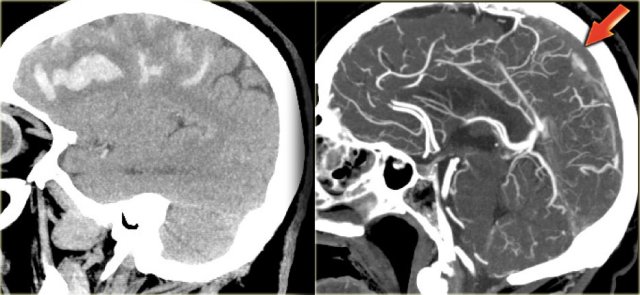

On the left reconstructed sagittal CT-images in a patient with bilateral parasagittal hemorrhage due to thrombosis of the superior sagittal sinus.

The red arrow on the contrast enhanced image indicates the filling defect caused by the thrombus.